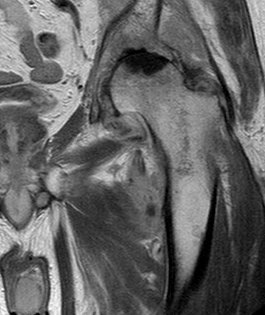

MRI is very sensitive but may still struggle to differentiate between advanced sepsis and AVN.

Aspiration of the hip joint, with x-ray control is the diagnostic test of choice. Staphylococcus aureus continues to be the most common organism isolated from adult hips affected by sepsis. Rarely, spontaneous nongonococcal and Candida sepsis of the hip joint in otherwise healthy adults have been reported.  Gonococcal septic hip arthritis is less common, and it is usually associated with specific host risk factors.